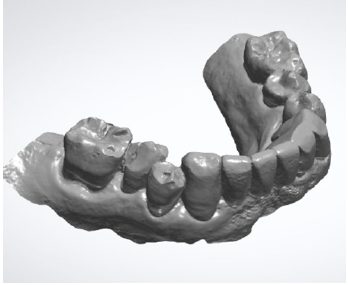

The second case shows the prosthetic rehabilitation of

a male patient suffering from periodontal disease, with five

periodontally compromised anterior teeth in need of extraction.

This case was elaborated in complete digital workflow. A static

guide was designed and manufactured based on cone beam

computed tomography (CBCT) images and intraoral digital scans,

in order to carry out a prosthesis guided surgery.

Before surgery, two mini-implants combined with the

associated skeletal scan bodies were placed in the distal sectors

of the maxilla. Three intraoral digital scans with the skeletal

scan bodies in place were taken: a scan of the maxillary arch, a

scan of the mandible, a scan of the patient’s habitual occlusion in

maximum intercuspation (Figures 13A & 13B).

Figure 13A: Digital impression of the maxillary arch and the scan bodies in place.

Figure 13B: Digital impression of the maxillomandibular relationship of patients’ habitual occlusion in maximum intercuspation.